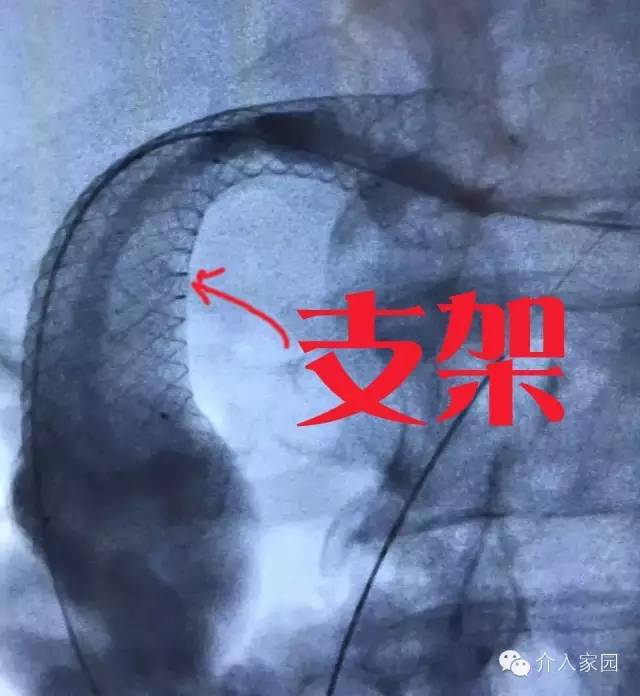

這個時候,化療放療切除都顯得那么的無助,腫瘤君可以囂張地宣告,它要慢慢折磨患者,讓他們不能喝水,不能吃飯,活活餓死患者!當然,如果沒有“介入治療”的話,它就可以實現(xiàn)目的了,但是,在開展了介入治療的醫(yī)院,可以很輕松地解決問題!不需要特別復雜的操作,在腫瘤堵塞的地方,通過一根管子或是放一個支架,就可以解決這個問題!

那介入治療怎么做?其實很簡單,放一個食管支架,食物和水就能夠通過支架進入胃了,如下圖,這個患者放了支架后,黑色的造影劑就通過支架往下流了?;颊哂帜苓M食了!雖然不能直接消滅腫瘤,但是可以讓患者在剩下的日子里更有尊嚴地活著!